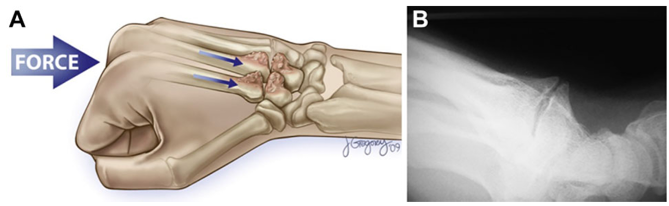

정확한 발생 원인은 미상이나, 외상(손상), 반복적인 손목의 움직임(스포츠, 작업 등), 선천적 부골(Os styloideum)과 관련이 있습니다.

※Os styloideum은 손목의 부골(accessory ossicle) 중 하나로, 주로 두 번째와 세 번째 중수골의 기저부 사이, 그리고 작은마름뼈(trapezoid)와 알머리뼈(capitate) 사이에 위치하는 작은 뼈 조각입니다. 일반적으로 움직이지 않으며, 정상 해부학적 변이로 간주됩니다.